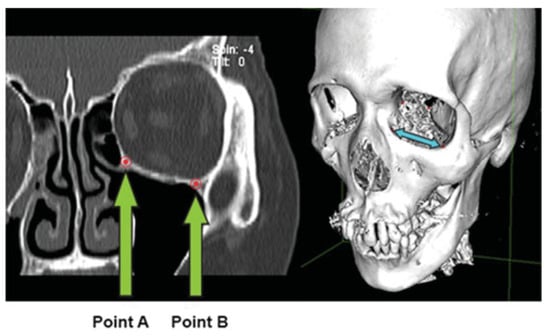

Figure 5.

Marking out the edges of the fracture. (a) Left orbital floor fracture with fracture size measured from the superior aspects of the fracture limits. (b) Stacking the reconstructed axial views onto each other by increasing the slab thickness, to view all the points of interest in a single layer. (c) Magnifying the area bounded by the points of interest by zooming in such that it fits the entire screen, to get a more accurate measurement by taking into account any irregular edges.

Figure 6.

Connecting the previously placed points of interest and measuring the area bounded by them to get the surface area of the defect.

There are advantages to our methodology. First, only basic clinical and computer knowledge is required to make the relevant measurements. As mentioned earlier, the quantitative portion of this protocol has been shared by Schouman et al, [] who obtained consistent measurements by three specialists using the CT scan images of 10 patients. By introducing a qualitative portion for the detection of orbital fractures, as well as modifying the quantitative portion by adding additional details such as magnifying the area bound ed by the points of interest (Figure 5), we were able to obtain consistent measurements by 15 independent observers who had no prior experience in reading CT scan images. Second, one only needs a basic CT viewing software program that allows linear measurements to be made (OsiriX; Pixmeo), therefore minimizing costs as no additional software needs to be purchased. Third, our protocol facilitates the measurement of orbital wall defects with a lower degree of interobserver variability. Fourth, it takes less time compared with other methods [,], as all our observers took approximately 3 minutes for each measurement. This includes the time taken for identifying the fracture and for making the measurements. Fifth, one does not need a high-resolution monitor to make the surface area measurements. The display resolution and PPI of monitors generally range from 1,280 × 800 and 113 pixels, respectively, on a 13-inch monitor to 2,880 × 1,800 and 220 pixels, respectively, on a 15-inch monitor. We could obtain surface area measurements on a low-resolution monitor by placing relevant points of interest on the CT coronal images without encountering any difficulty. Therefore, one does not need a high-resolution monitor and can make with any low-resolution monitor that is available in the market.